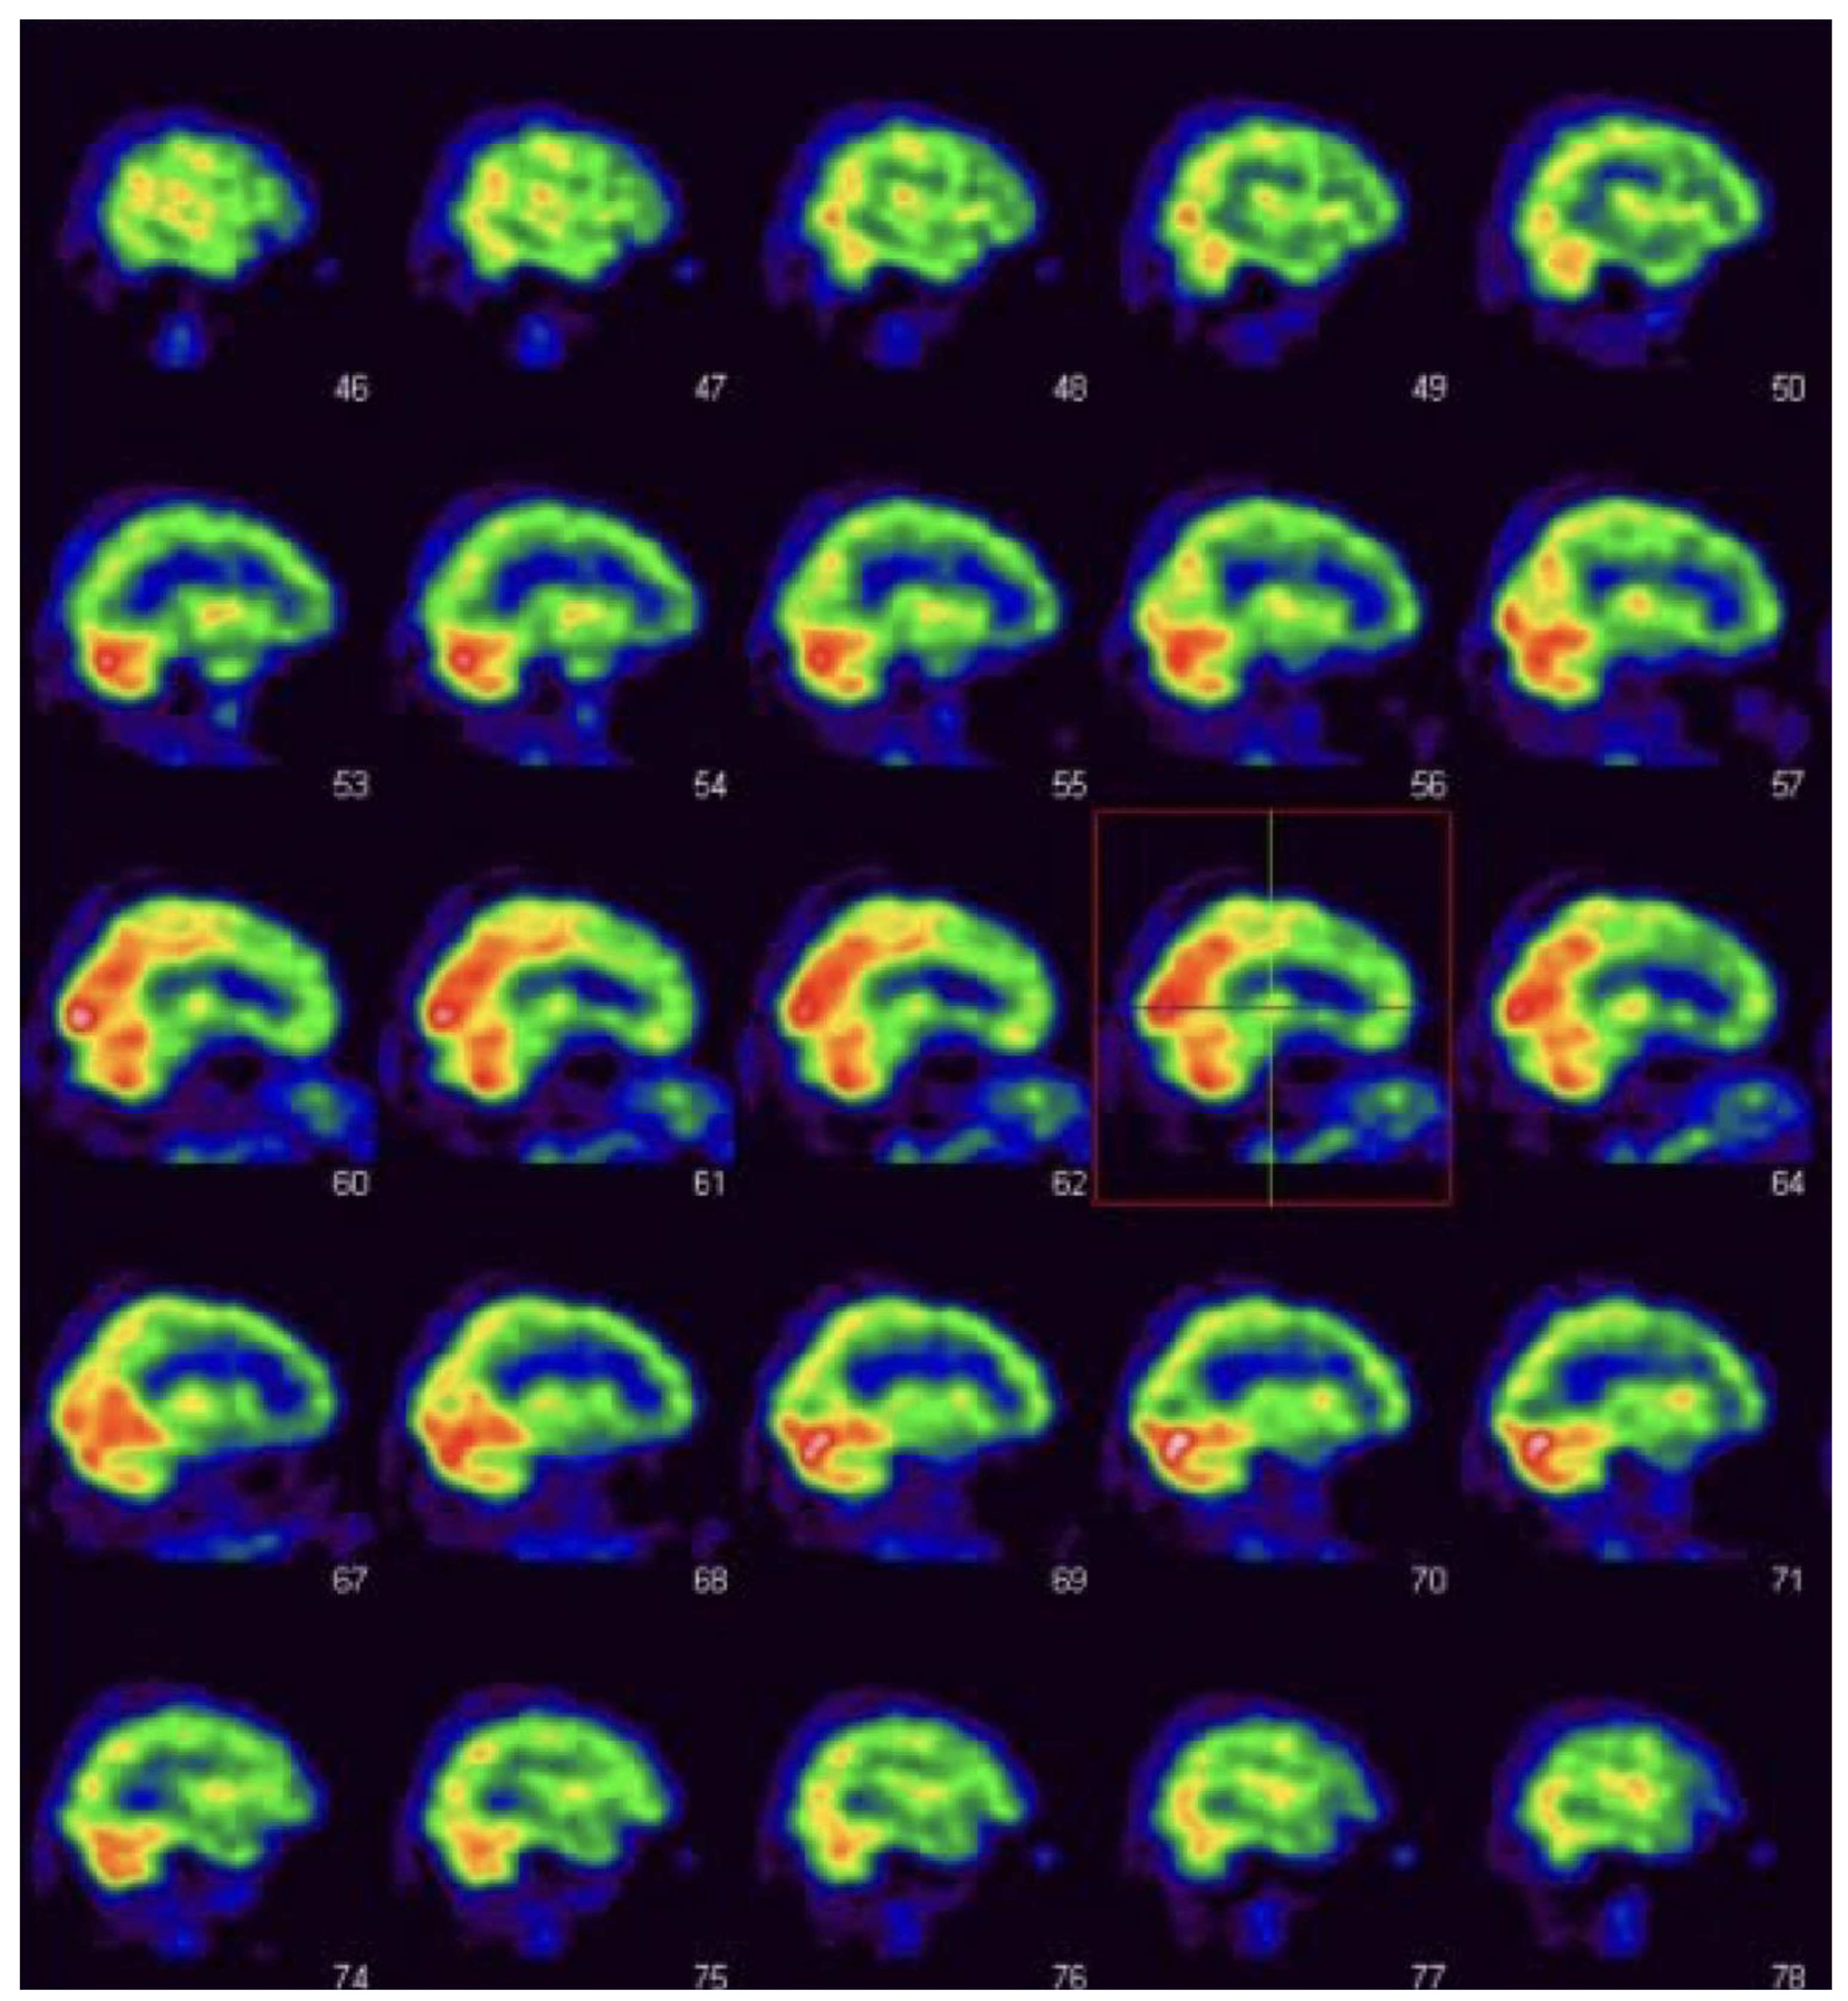

2.2. SPECT

Alster, P.; Madetko-Alster, N.; Migda, B.; Nieciecki, M.; Koziorowski, D.; Królicki, L. The Assessment of Subregions in the Frontal Lobe May Be Feasible in the Differential Diagnosis of Progressive Supranuclear Palsy—Parkinsonism Predominant (PSP-P) and Multiple System Atrophy (MSA). Diagnostics 2022, 12, 2421. https://doi.org/10.3390/diagnostics12102421